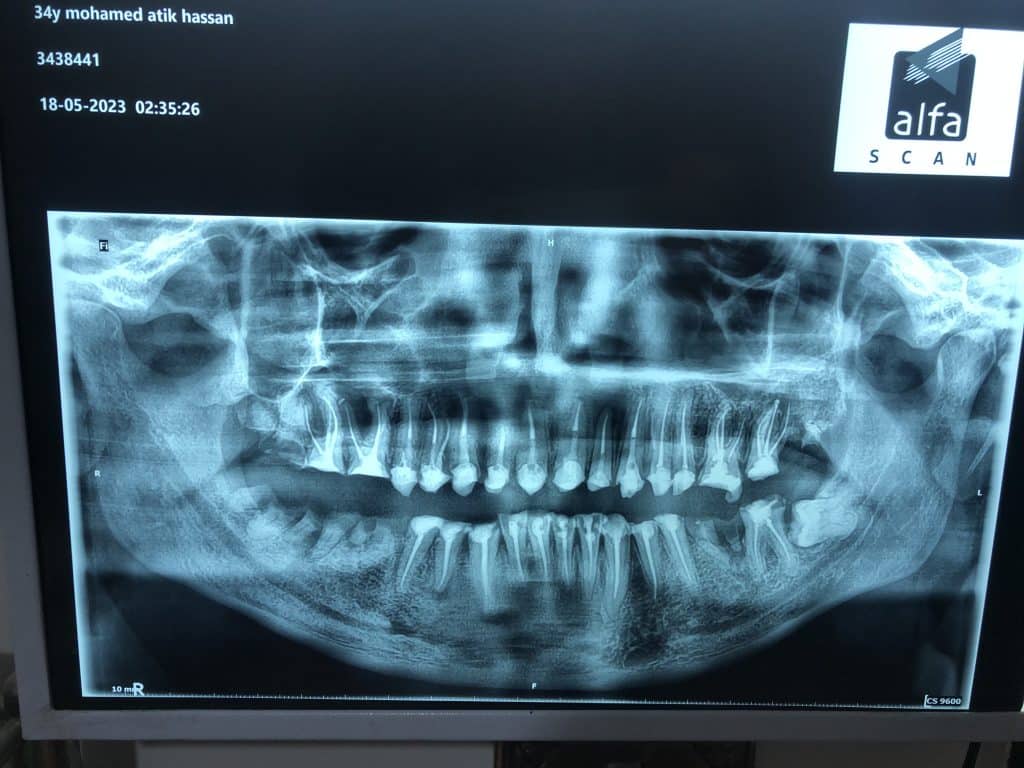

The diagnostic aid : panoramic x-ray , clinical examination .

2- remove all caries from all teeth , RCT and re RCT for all treated teeth

( 11,12,13,14,15,16,17,21,22,23,24,25,26,27,31,32,33,34,35,41,42,43,44,45)

3- extraction for lower left and right 6 molars and 7 lower left molars and immediate implanting for 6 lower left and 7 lower right ( immediate loading fro MONO Implant Swiss implants .

4- obturation of all canals by WellRoot Bioceramic sealer (crown down technique and single cone ) for ( 11,12,13,14,15,16,17,21,22,23,24,25,26,27,31,32,33,34,35,41,42,43,44,45 )

5- after post-obturation panorama … re_RCT for 32-33